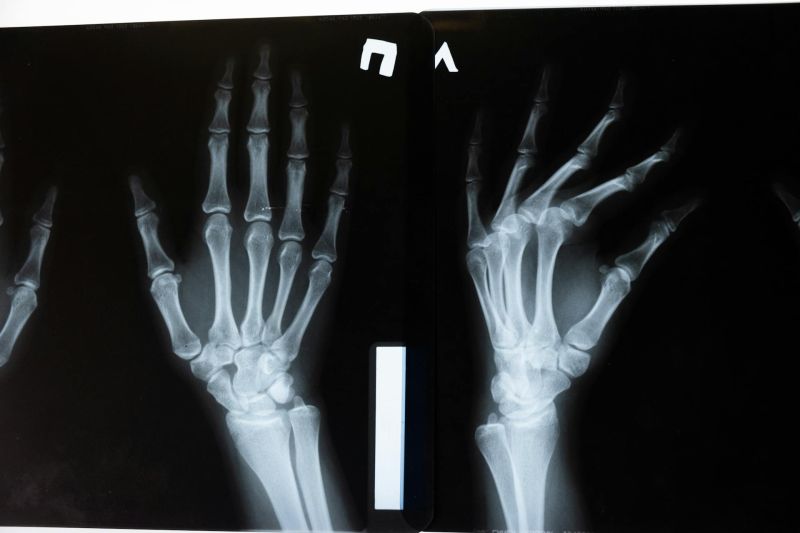

Multislajsni CT pregled zglobova omogućava detaljan prikaz zglobnih struktura i okolnih tkiva, uključujući kosti, hrskavicu, tetive, ligamente, mišiće i krvne sudove. Ova dijagnostička metoda koristi rendgenske zrake i naprednu računalnu obradu kako bi se dobile precizne presečne slike, koje se po potrebi mogu prikazati i u trodimenzionalnom obliku.

Multislajsni CT omogućava veoma precizno sagledavanje struktura zgloba, uključujući i sitne promene koje drugim metodama mogu ostati neprimećene. Po potrebi se koristi kontrastno sredstvo radi boljeg prikaza krvnih sudova i mekih tkiva.

• traumatske povrede i sitne frakture